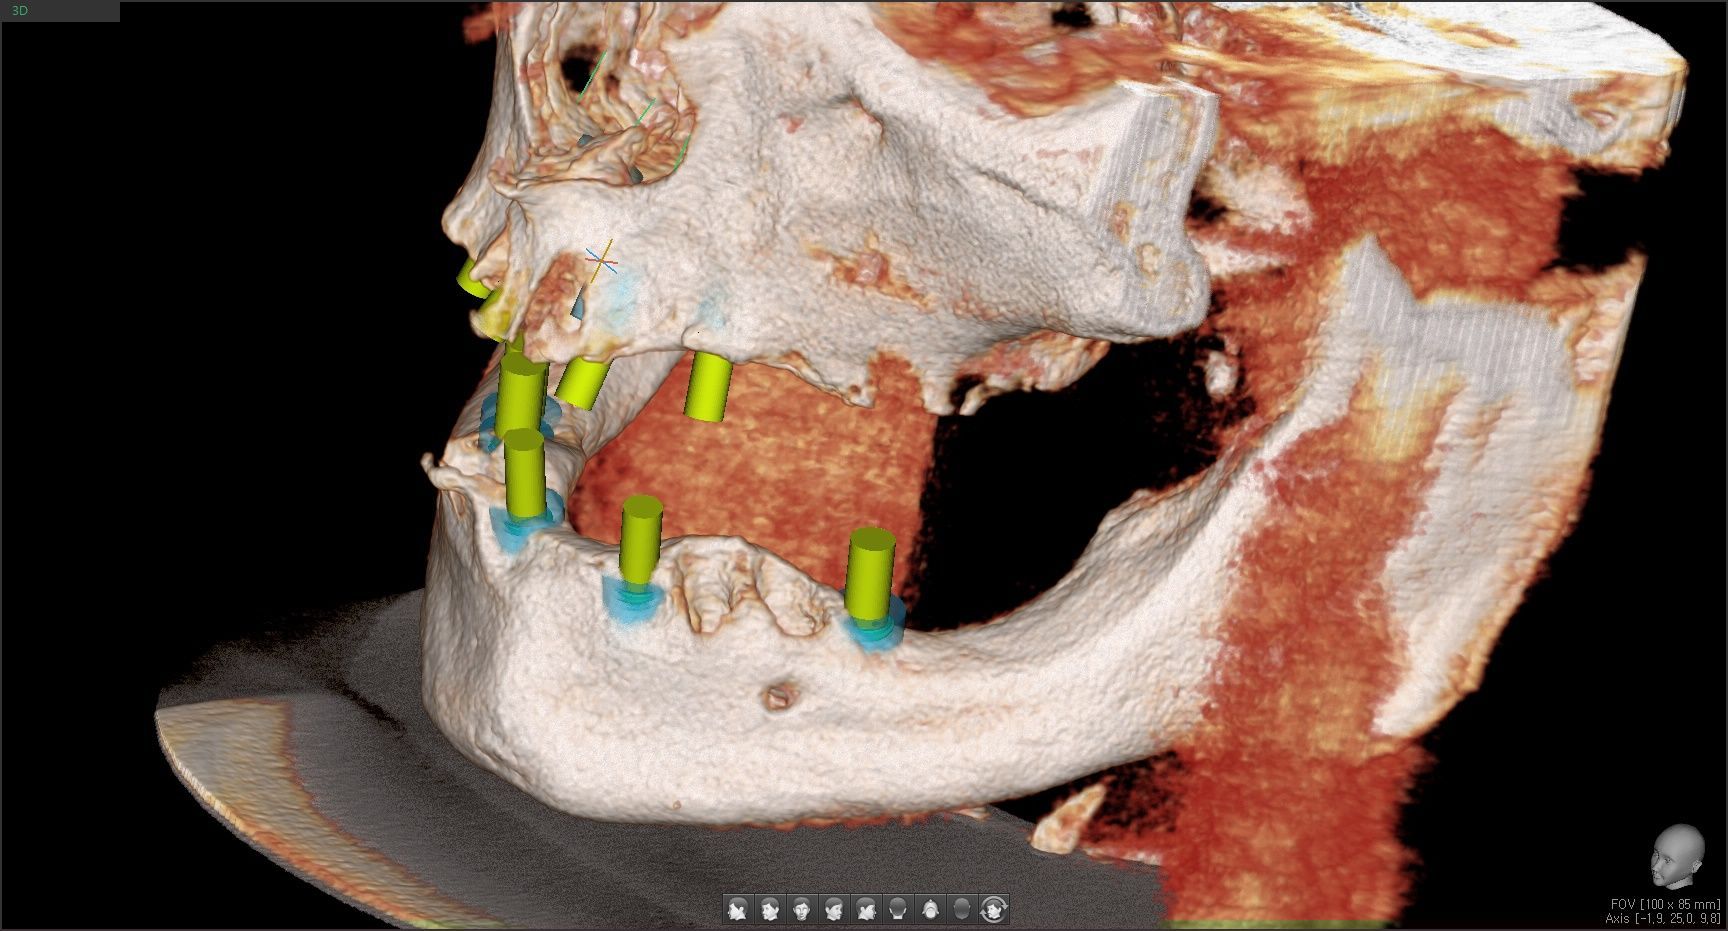

This image shows multiple implants placed in the maxilla.

Because the maxillary bone is relatively soft, achieving strong primary stability

at the time of placement is especially important.

Bone grafting was performed where necessary, and adequate healing

time was allowed afterward to ensure successful osseointegration.

This image shows the implants placed in the planned positions on both the right and left sides of the mandible.

Although the mandibular bone is denser than the maxillary bone, many areas lie close to the nerve canal, making careful selection of implant angulation and length essential.